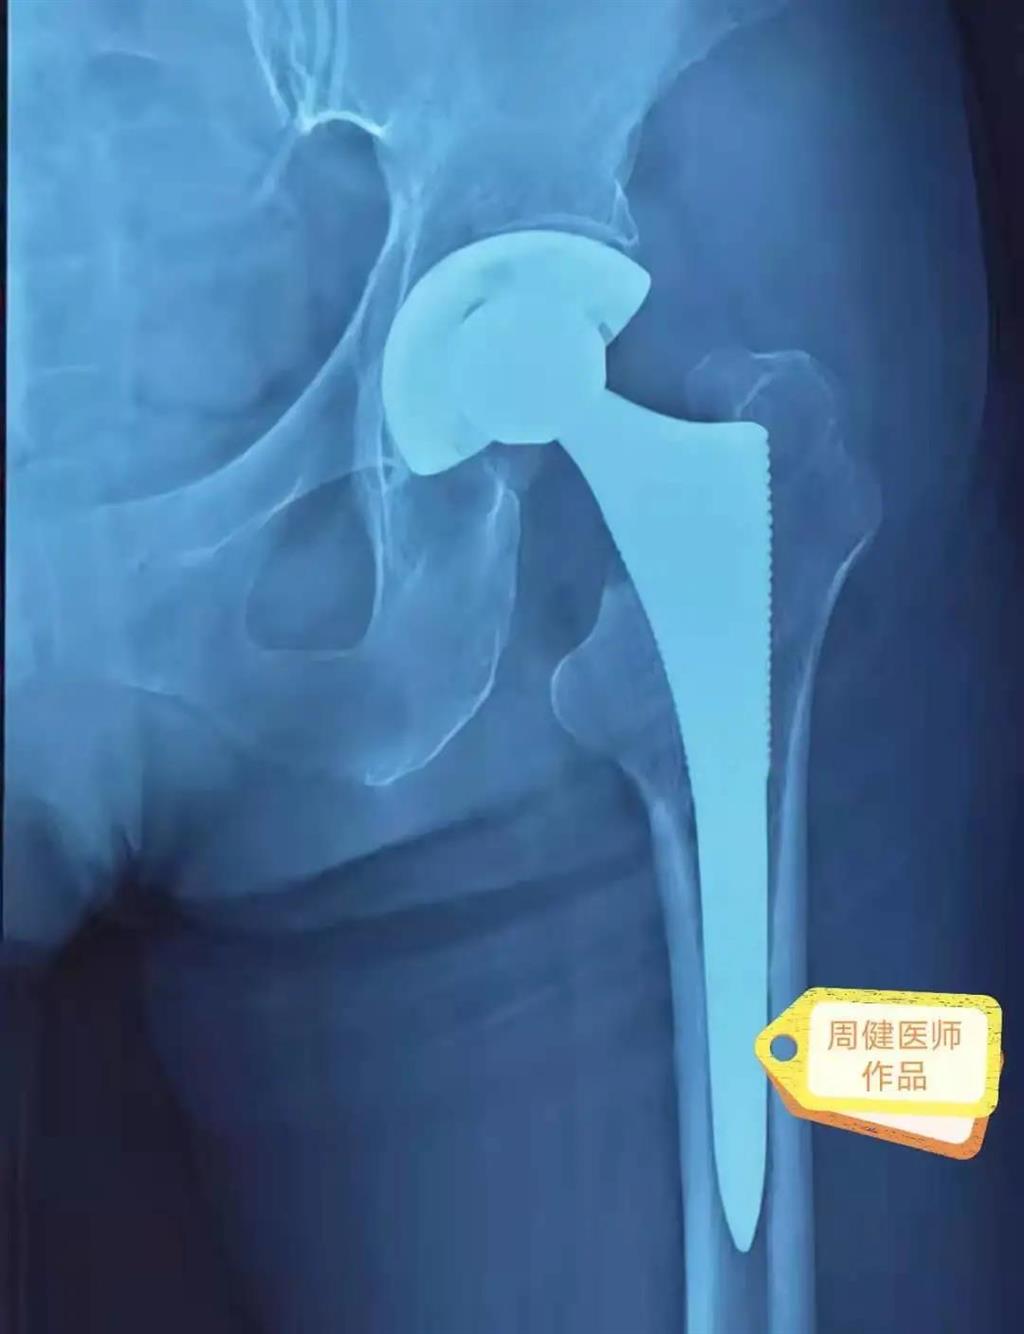

6月30日的“關(guān)節(jié)置換術(shù)”,患者是一位上了年紀(jì)的老人,苦于病痛折磨多年的他四處“求醫(yī)問藥”,最后在多位專家醫(yī)師及病友地力薦下選擇了和平國(guó)際醫(yī)院,在醫(yī)師團(tuán)隊(duì)“偷天換日”般的手術(shù)后,老人成功告別了苦纏多年的病痛。

周健說,這場(chǎng)“關(guān)節(jié)置換術(shù)”對(duì)于他們團(tuán)隊(duì)而言其實(shí)算是比較普通的手術(shù),因?yàn)樽鲞^很多同類的手術(shù),成功案例繁多,因此在手術(shù)操作上有較多地實(shí)操經(jīng)驗(yàn)。“不過話雖如此,作為醫(yī)生我們對(duì)于每一場(chǎng)手術(shù)都會(huì)全力以赴,這是為醫(yī)者的職責(zé)也是義務(wù)。”